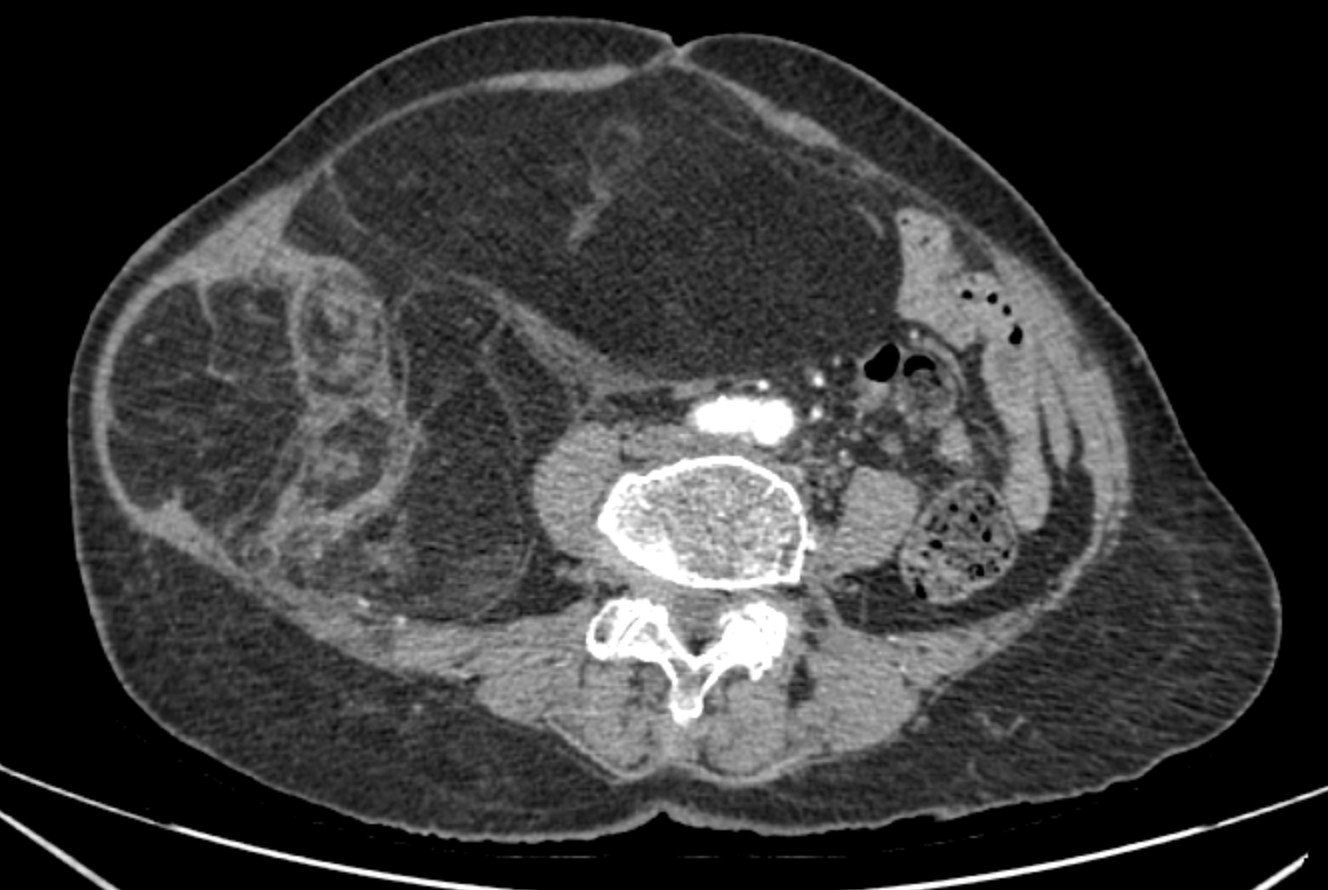

Phim chụp CT ổ bụng của bệnh nhân.

Chẩn đoán hình ảnh (CT ổ bụng có thuốc cản quang) cho thấy khối choán chỗ sau phúc mạc, kích thước 28 × 15 cm, cấu trúc hỗn hợp tổ chức mỡ – đặc , đè đẩy tạng trong ổ bụng nhưng không có dấu hiệu xâm lấn các tạng lân cận. Kết hợp lâm sàng và hình ảnh học, bệnh nhân được chẩn đoán sarcoma mỡ sau phúc mạc.

Ca bệnh được đánh giá nguy cơ cao do tuổi bệnh nhân lớn, bệnh lý hô hấp nền và khối u kích thước khổng lồ thâm nhiễm cơ thành bụng. Nguy cơ mất máu nhiều và rối loạn huyết động trong mổ được tiên lượng. Sau hội chẩn đa chuyên khoa, bệnh nhân được chỉ định phẫu thuật cắt bỏ triệt để khối u.

Ekíp phẫu thuật mở bụng theo đường giữa trên – dưới rốn mở rộng sang phải, vết mổ dài khoảng 30 cm. Trong mổ ghi nhận khối màu vàng nhạt, thâm nhiễm cơ thắt lưng phải, chưa xâm lấn tạng tuy nhiên u ranh giới không rõ, len lỏi giữa các tạng và cân cơ thành bụng nên phẫu tích gặp nhiều khó khăn.

Phẫu thuật viên tiến hành bóc tách cẩn trọng theo mặt phẳng giải phẫu, kiểm soát các nhánh mạch nhỏ, tránh tổn thương tạng lân cận. Toàn bộ khối u được lấy ra nguyên vẹn, nặng gần 4 kg, kích thước 28 × 15 cm. Lượng máu mất ước tính < 300 ml, không cần truyền máu trong mổ.